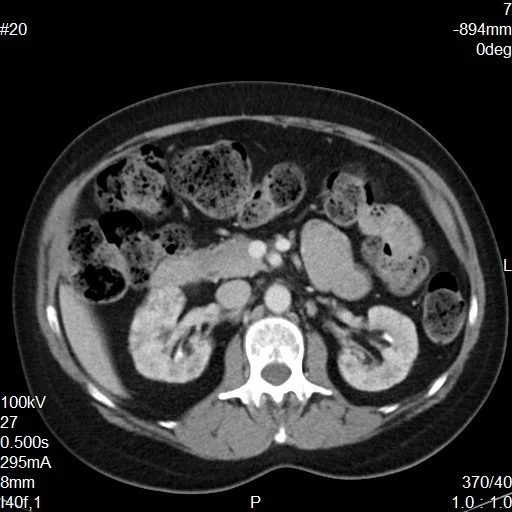

Lithium Nephrotoxicity

• Basically multiple bilateral renal cysts

• Duration of lithium therapy increases the risk of ESRD